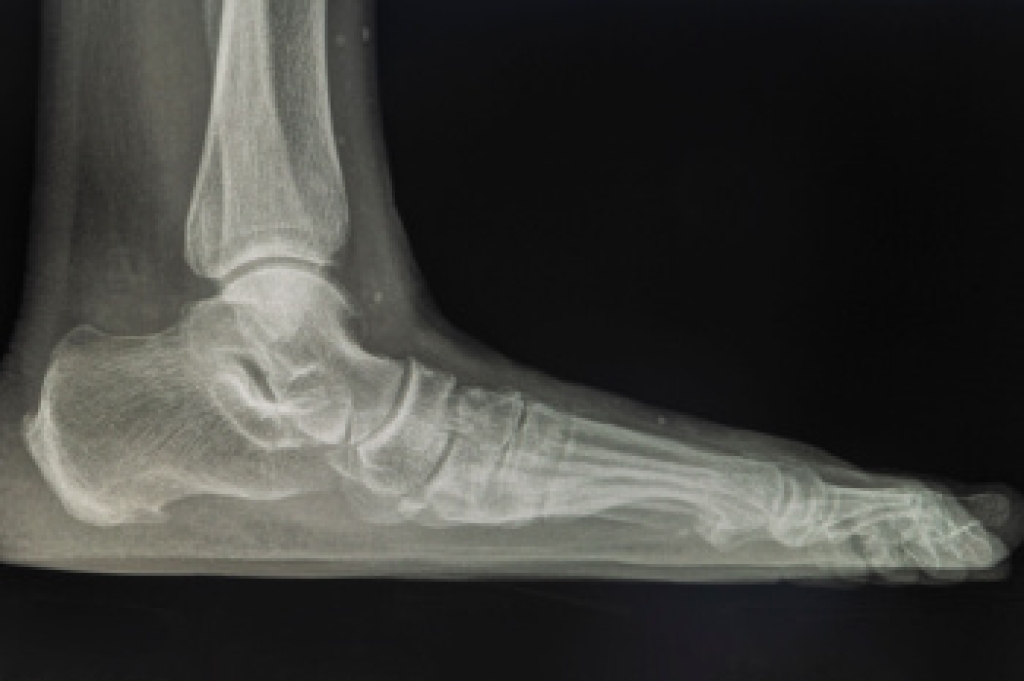

Limb salvage teams have grown in recent years that utilize a number of different treatments to save the infected limb. This includes podiatrists that specialize in wound care, rehabilitation, orthotics, and surgery. Through a combination of these methods, limb salvage has been found to be an effective treatment for infected limbs, and as an alternative to amputation. Podiatrists will first evaluate the potential for limb salvage and determine if the limb can be saved or must be amputated.